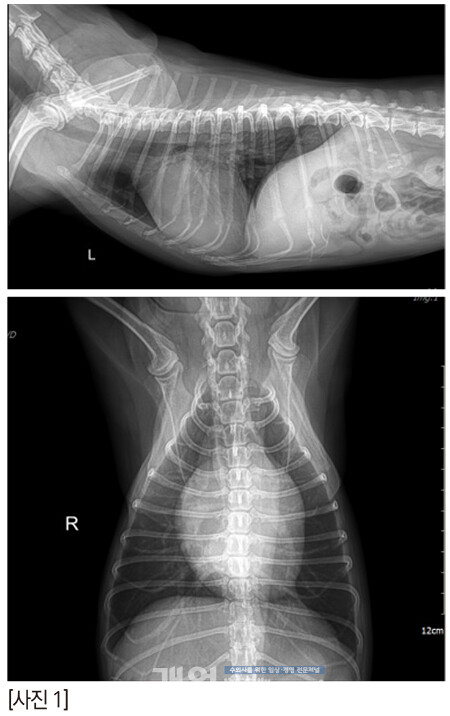

zone 2의 스틸컷이다. 어때 보이는가? 잘 닫히고 괜찮은가?

anterior leaflet의 끝단이 flail 되고 있다. 늘상 만나는 심각한 수준의 아이들 보다는 좀 낫긴 한데, 퇴행성 변화로 판막의 끝단이 너덜거리고, anterior leaflet의 건삭은 조금씩 닳아서 끊어지고 있나보다. 끝단이 좌심방을 향해 있다.

anterior의 zone 2-3과 posterior의 zone 2가 좀 뒤집어지고 있다. 이것은 건삭의 일부가 끊어져 너덜거리는 것으로 예측한다. 2D에서는 역류가 심해 보이지 않았지만 3D에서는 꽤 심해 보인다.